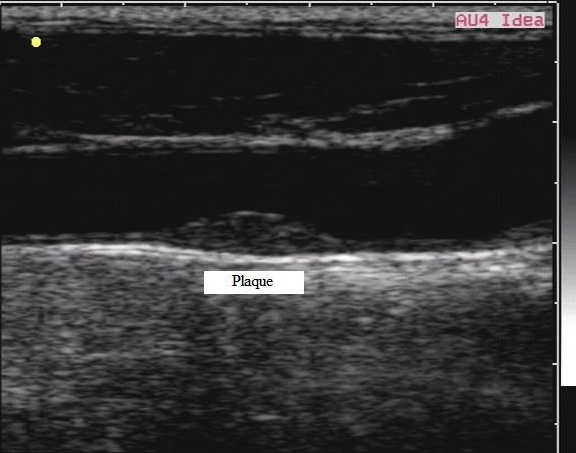

jbe2ur7k.jpg